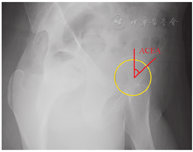

Cam型FAI首先通过骨盆正位X线片中股骨α角来初步评估。Nötzli等[19]描述α角是股骨颈轴所在的直线与一条连接股骨头中心点和股骨头正常球形截面发生改变的点的连线相交形成的夹角,当股骨头颈处有异常骨质凸起时α角增大。一般认为α角>50°~60°时为异常,国内学者多数把α角>55°作为Cam型FAI的标准,而国外的研究多认为α角应>60°[14,20,21,22,23,24,25]。α角通常被认为是评价FAI最可靠的影像学指标之一,α角量化了FAI的病理严重程度,可预测髋关节盂唇和软骨损伤程度[26,27]。Cam型FAI手术的主要目标之一是将α角恢复至<55°,有利于改善患者预后;术后α角≤46°的运动员回归运动的可能性是术后α角>46°的运动员的6.3倍[28,29]。但是考虑到FAI是一种三维骨性畸形病变,且α角经常在股骨头颈的前方或前上方增大最为显著,因此在骨盆正位X线片中测出的α角一般不能代表患者最明显的Cam型FAI。除α角外,股骨头颈偏移(off-set)和头颈偏移率(off-set ratio)的减小及枪柄样畸形也被认为是Cam型FAI的影像学特征。

标准45°Dunn位X线片可清晰显示股骨头颈的3点钟方向,即撞击较为明显的部位。Dunn位X线片的主要测量指标是α角和股骨头颈偏心距(图4)。股骨头颈偏心距指股骨头颈移行区至股骨颈之间的距离,正常为9~11 mm;股骨头颈偏移率为股骨头颈偏心距与股骨头直径的比值,正常应>20%,若偏心距和偏移率变小则说明股骨头颈移行处有异常隆起。一般认为股骨头颈偏移<8 mm或头颈偏移率<18%为异常,提示Cam型FAI[52]。